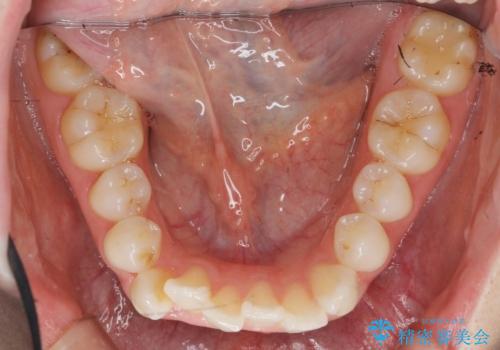

- 前歯が出っ歯のように見えることの改善を求めて来院されました。

当初、セラミックによる治療をご希望されていましたが、相談の結果矯正治療を選択されることとなりました。

通常口元の突出感の改善を行うには小臼歯の4本抜歯が検討されますが、歯のガタ付きが下顎前歯に限定していることから

下顎前歯を1本だけ抜去を行い、上顎の歯は可及的にマイクロインプラントを用いた後方移動を行い口元の印象の改善を計画することとなりました。